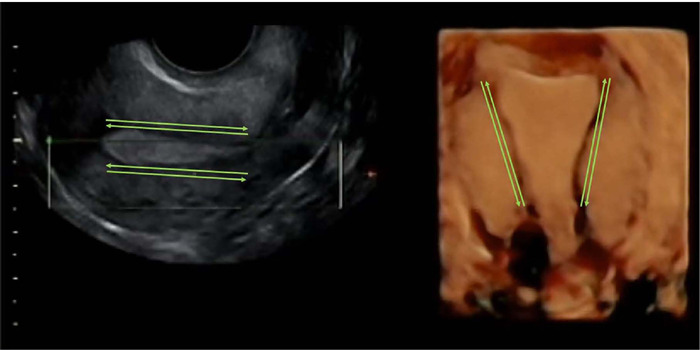

Methods: Prospective evaluation in patients undergoing frozen blastocyst embryo transfer in medicated endometrial preparation cycles. Twenty patients were included in groups: A/nulliparous. B/previous vaginal delivery. C/ previous CS without a niche, whereas fifteen patients were recruited in group D (CS and a niche). Patients employed estradiol compounds and 800 mg vaginal progesterone. A 3D-scan was performed the transfer-day where uterine contractility/minute was recorded.

Abstract Image